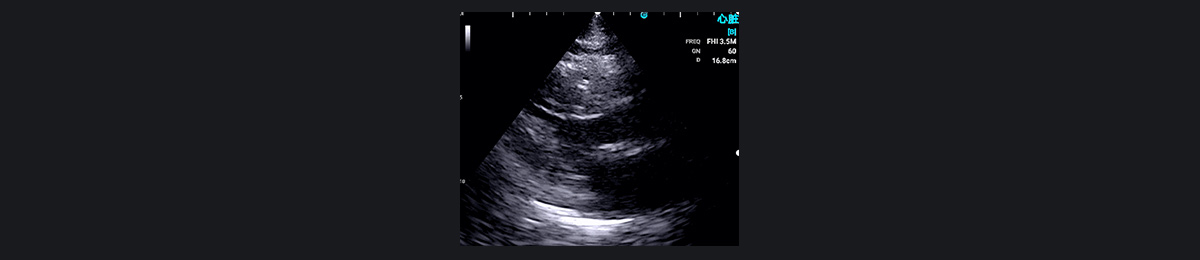

Ò»ÃûÖÐÄêÄÐÐÔ»¼ÕßÒò×ó²àÐØÍ´ÈëÔº¡£¿ìËÙÊÖ³Ö³¬ÉùɨÃ裨ÐļâËÄÇ»ÊÓͼºÍ¶ÌÖáÊÓͼ£©ÏÔʾÐļâºÍǰ±ÚµÄÔ˶¯ÏÔ׿õÉÙ£¬Ìáʾ ACS¡£Ë«Áª¿¹ÑªÐ¡°åÖÎÁÆËæºó½øÐÐ PCI ֤ʵ×óǰ½µÖ§¶¯Âö±ÕÈû¡£

³ÉÈËÐØÍ´Í¨³£ÊÇÓɹÚ×´¶¯Âö¼²²¡ÒýÆðµÄ£¬µ«È·¶¨È·ÇÐÔÒòÐèÒª½øÒ»²½µ÷²é¡£Í¨¹ý³¬Éù²¨³ÉÏñ£¬SonoEye ÊÖ³Öʽ³¬Éù²¨¿ÉÒÔÇø·ÖÐØÍ´ÊÇ·ñÊÇÐÄÔ´ÐԵġ£ËüÔÚÕï¶ÏÐÄѪ¹ÜÒì³£·½ÃæÌرðÓÐЧ£¬ÀýÈç·ÊºñÐÔ¹£×èÐÔÐ¡¡¢Ö÷¶¯Âö°êÏÁÕ¡¢Ö÷¶¯Âö¼Ð²ã¡¢ÐİüÑס¢¶þ¼â°êÏÁպͷÎ˨Èû¡£

·ÊºñÐÔ¹£×èÐÔÐ¡